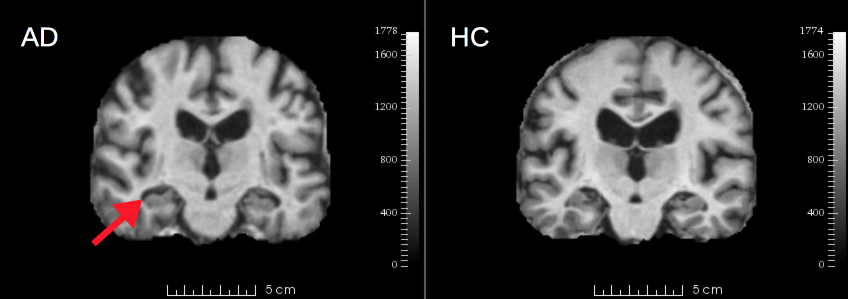

Neuroimage classification here is based on the publicly available OASIS dataset [25] consisting of brain MRIs from 416 unique, right-handed individuals spanning an age range of [18,96] years, with approximately equal numbers of male and females. We investigate binary classification in two contexts: 1) Alzheimer’s disease (AD) vs. healthy controls (HC) 2) and old vs. young subjects. In general, both Alzheimer’s disease and natural aging are characterized by cortical atrophy and enlargement of extra cerebral spaces. AD in particular is linked to cortical atrophy about the hippocampus, a neuroanatomical structure intimately linked to short-term memory storage which is impaired in AD sufferers. Figure 2 illustrates subtle differences between AD and HC brains surrounding the hippocampus, and the challenge of AD vs. HC classification.